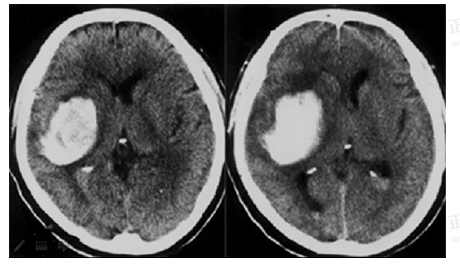

男55岁,左侧肢体偏瘫4小时,有高血压史,诊断为

A.急性硬膜下血肿

B.急性硬膜外血肿

C.颅骨骨折

D.急性脑梗死

E.急性脑出血

【答案】E